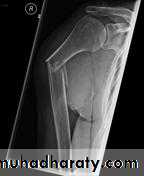

Fracture shaft of humerus:

Traumatic & pathological3-5% of all fractures

Fracture location: proximal, middle or distal third.

Fracture pattern: spiral, transverse, comminuted or oblique.

X-ray: to show types & site of fracture.